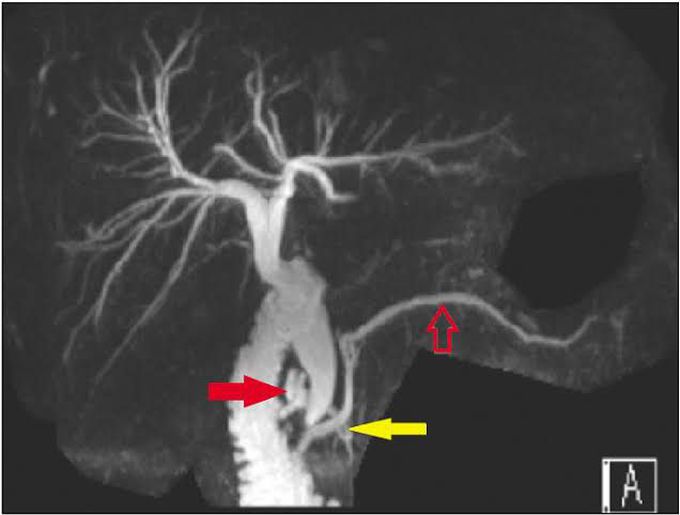

[A], resonance cholangiopancreatography (MRCP) before initial Magnetic Resonance Cholangiopancreatography In Spanish A magnetic resonance cholangiopancreatography (mrcp) is an imaging test to examine your pancreatic. la colangiopancreatografía por resonancia magnética tiene las siguientes características: It provides similar views of the bile ducts, but is not always possible to. a magnetic resonance cholangiopancreatography (mrcp) scan is a medical scanning method that uses radio waves and a magnetic field to give clear. Magnetic Resonance Cholangiopancreatography In Spanish.

resonance cholangiopancreatography with maximum intensity